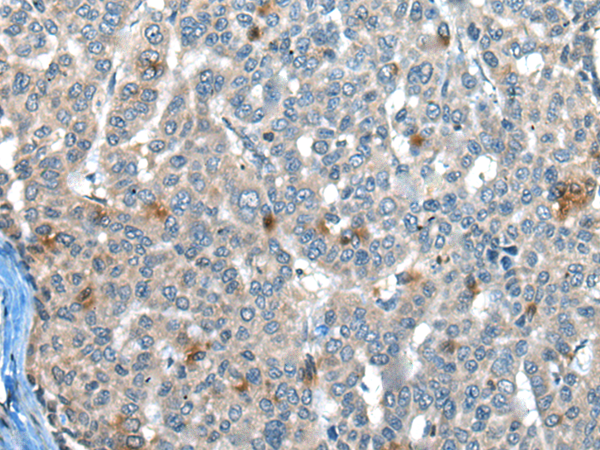

分类: 科研抗体货号: P00259别名: P21; CIP1; SDI1; WAF1; CAP20; CDKN1; MDA-6; p21CIP1应用: WB,IHC反应种属: Human